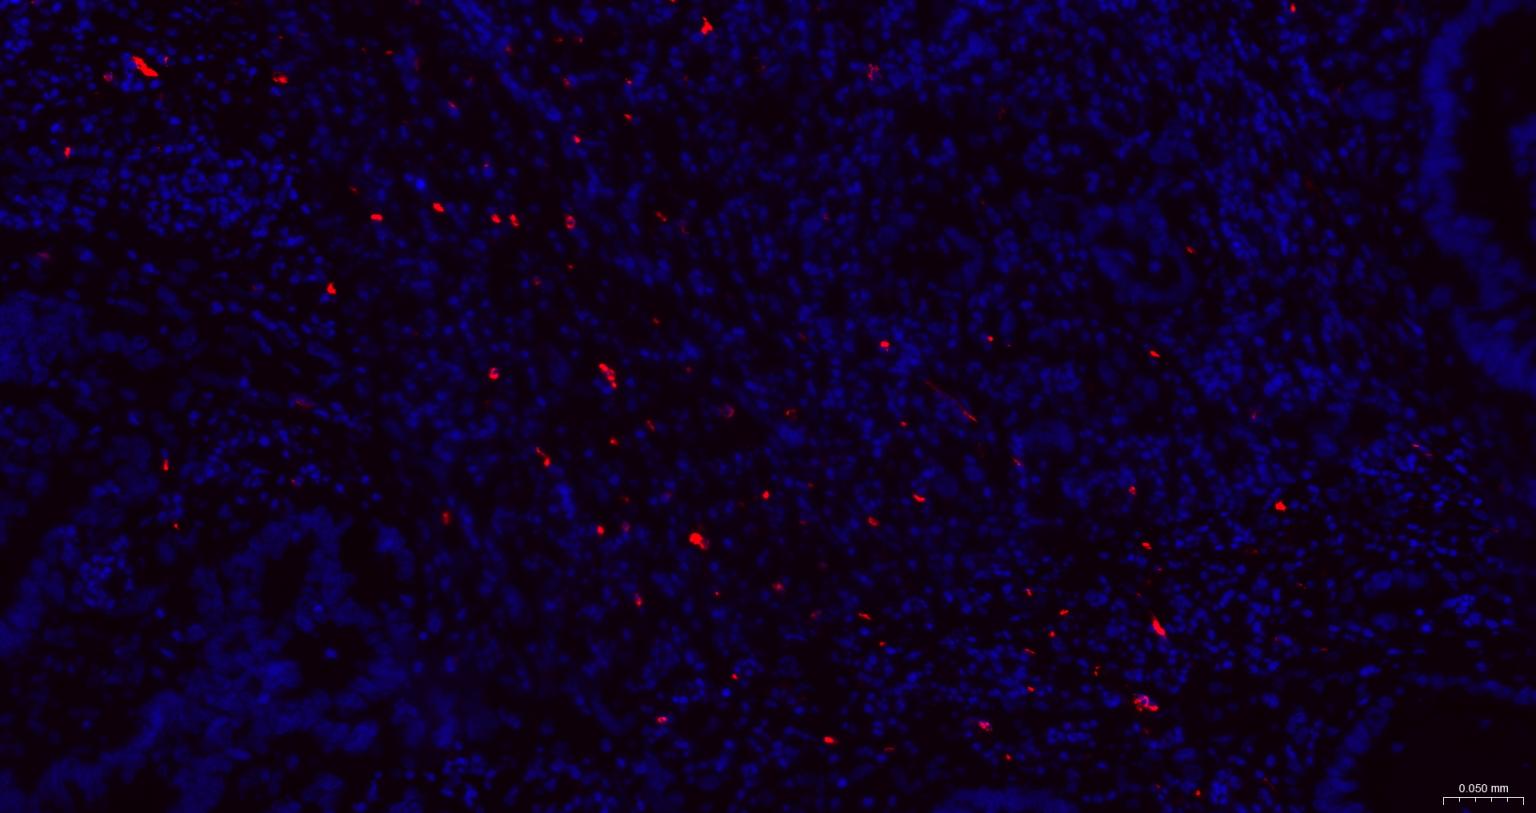

Paraformaldehyde-fixed, paraffin embedded Human Colon Cancer; Antigen retrieval by boiling in sodium citrate buffer (pH6.0) for 15 min; The section was incubated with Granzyme B Monoclonal Antibody, Unconjugated (bsm-60779R) at 1:200 overnight at 4°C. Followed by conjugated Goat Anti-Rabbit IgG antibody (Red, bs-0295G-BF594), DAPI (blue, C02-04002) was used to stain the cell nuclei.